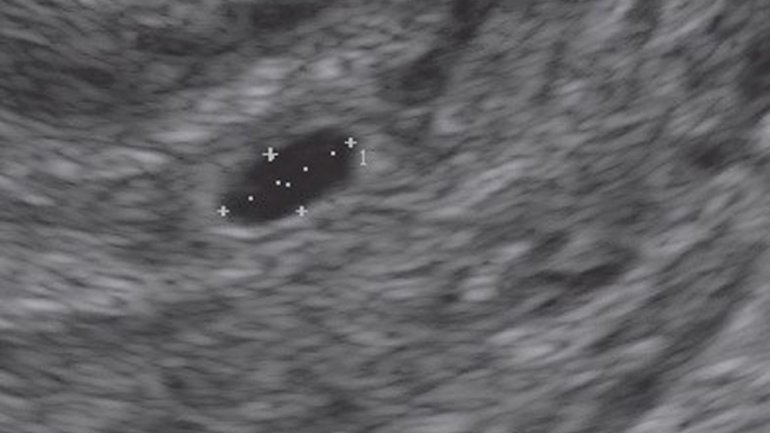

Ultraschall 4. SSW

In der 4. Schwangerschaftswoche nistet sich die befruchtete Eizelle in der Gebärmutter ein. In dieser Phase der Frühschwangerschaft ist nur die Fruchthöhle (schwarz) zu sehen, da der Embryo noch zu klein ist. Das restliche Bild zeigt die gut aufgebaute Gebärmutterschleimhaut (Endometrium), in der sich die Eizelle einnisten kann.